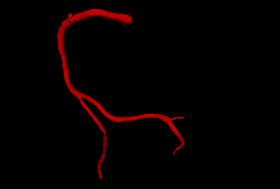

| Centerlines of polydata models can be computed using the VMTKCenterlines module. Beside the actual centerline it also outputs the Voronoi diagram which describes the maximal sphere radius of every point on the centerline. The module also provides import and export functionality for centerlines defined by a cloud of points.

This step closes the input model with caps and changes the color to green. Centerlines Computation:

After computation, the centerlines and Voronoi diagram are added as 3D polydata models to the current scene and get displayed in the 3D rendering window. Import/Export: Computed centerlines can be imported and exported as clouds of points.

We imported the reference centerline for the RCA (expert segmentation, provided by [Schaap2009]) and added it to the 3D Slicer scene.